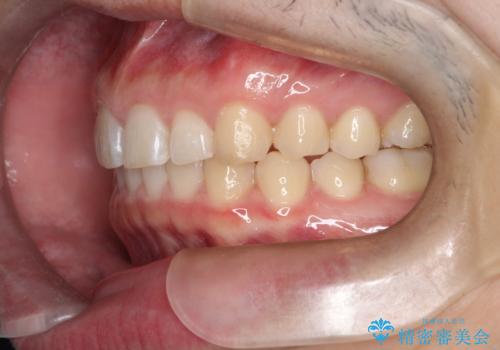

[ インビザラインライト ] 短期間で前歯だけを並べたい

担当医 大元洋佑